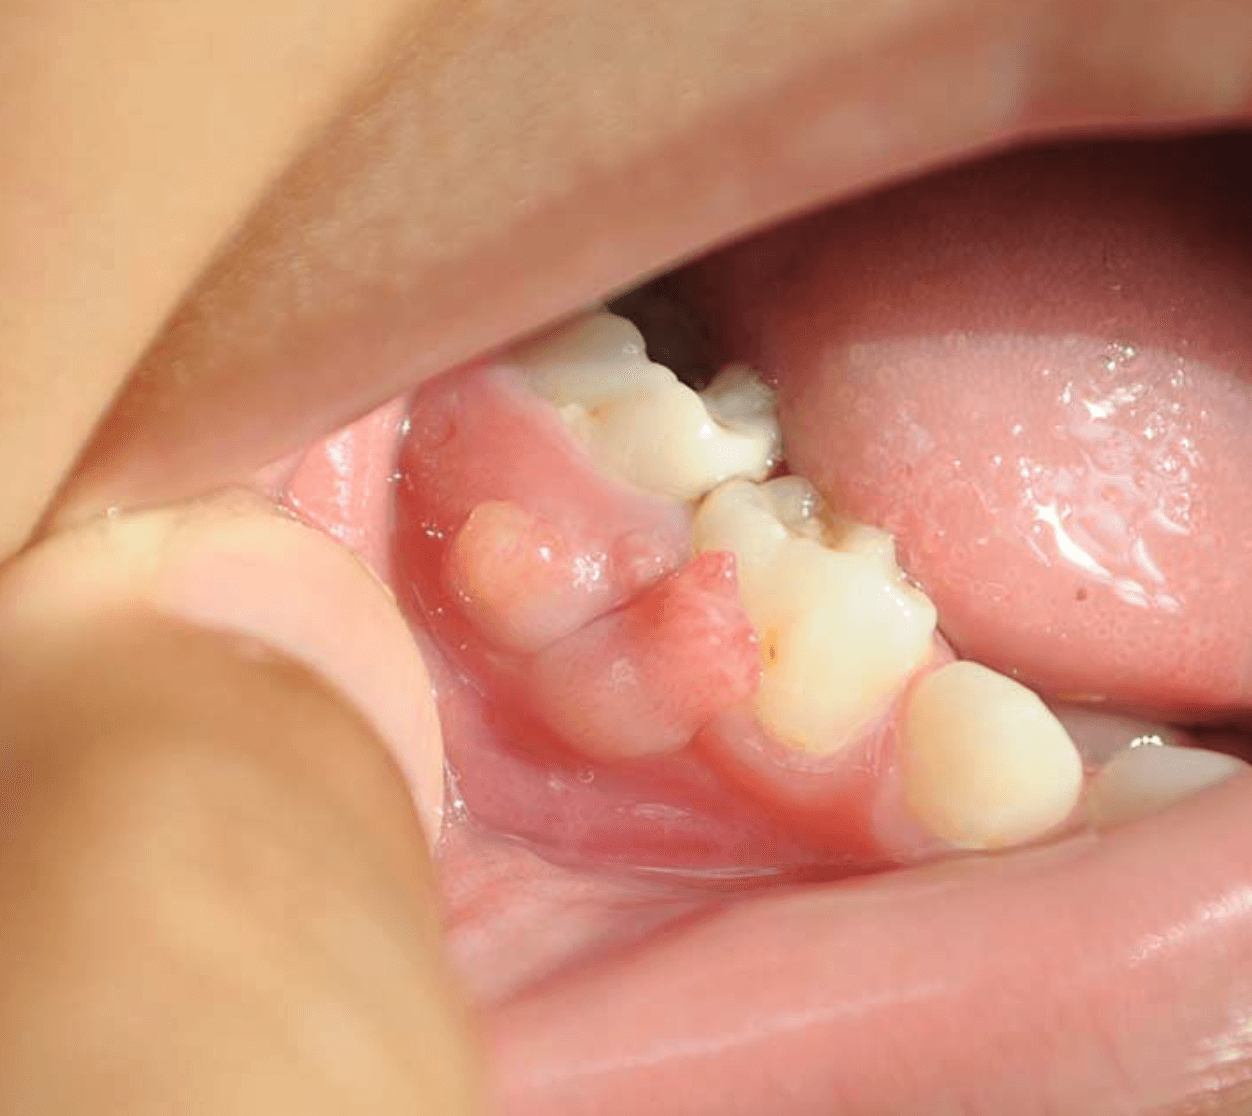

잇몸 고름주머니 발치

치아를 발치하게 되는경우는 잇몸뿌리에 염증이 너무 심해서 다른 치아까지 피해를 주는경우 다른 치아라도 빨르게 살리기 위해 치아를 뽑고 치료를 할수 있습니다. 그러나 보통 신경치료를 통해 염증을 치료하지만 신경치료를한 치아에 또다시 고름주머니가 생기는 경우 잇몸을 절개하여 배농한후 상황을 지켜봐야 합니다.

항생제와 치료를 하고도 계속 재발하는경우 치근단절재술과 재 신경치료를 통해 치아 뿌리 및 주변 치주 농양을 잡고 주기적인 검진을 할수 있습니다. 글쓴이가 치근단절제술을 한지 1년이 되었는데 다시 잇몸 고름주머니가 생겨, 치과의사는 한번더 잇몸을 절개하고 치료를 하자고 하는데, 글쓴이는 잇몸수술이 생각보다 통증이 심해서 고민을 하고 있습니다.